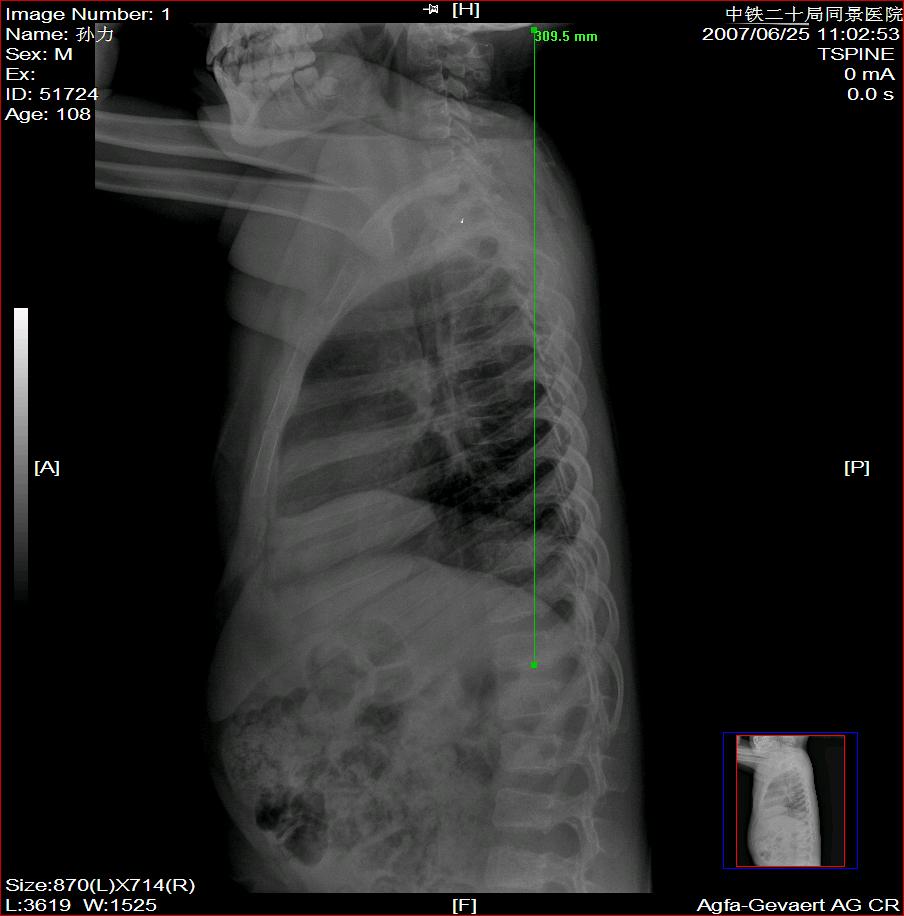

标题: X2504:M17Y,高中生,身高不足1.2米,智力正常 [打印本页]

标题: X2504:M17Y,高中生,身高不足1.2米,智力正常

年龄17岁,身材矮小(1.2m),全身骨骼发育迟缓,骨骺线仍较宽,但全身骨骼骨质正常,智力正常。

骨结构正常,骨骺线与17岁不符,豆状骨未见,相当7-8岁骨龄,结合智力正常,垂体性侏儒可能大。

考虑垂体侏儒的可能。依据1骨龄延迟,骨胳结构正常,智力正常。与甲状腺功能不足区别呆小症病人长骨及骨垢有改变,骨垢较正常小。椎体变扁。考虑垂体侏儒症。

各部比例在正常范围,为均称型侏儒,可见于1、垂体性侏儒。2、致密性骨发育不全。3、turner氏综合症。本例骨密度正常,皮质边界清,显然不支持致密性骨发育不全,未见掌骨征阳性和指骨优势,turner氏综合症,可基本除外,剩下的只有垂体性侏儒了,建议垂体mri进一步检查,确定诊断。以上主要参考曹来宾教授发表的论文,侏儒症的临床x线分析

全身骨骼发育迟缓,骨骺线仍较宽与年龄不符。考虑垂体性侏儒可能大。